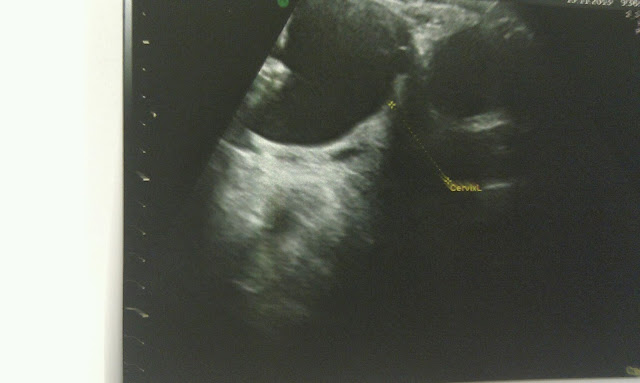

Num dia que começou com a M. acordada às 6:15 da manhã (muito alegre) porque queria ver a mana (ecografia que só seria às 8:50) nada faria prever o maravilhoso sol... O sol que iluminou o percurso até ao Hospital, onde ansiosos esperávamos para ser chamados para a Ecografia.

A eco foi feita... crescimento normal, percentil 50... é isto que quero guardar do meu dia. As partes menos boas guardo-as (por enquanto) somente para nós. São menos boas porque assim as entendo... provavelmente para outra não seriam!

| A "maninha" como lhe chama a M, |